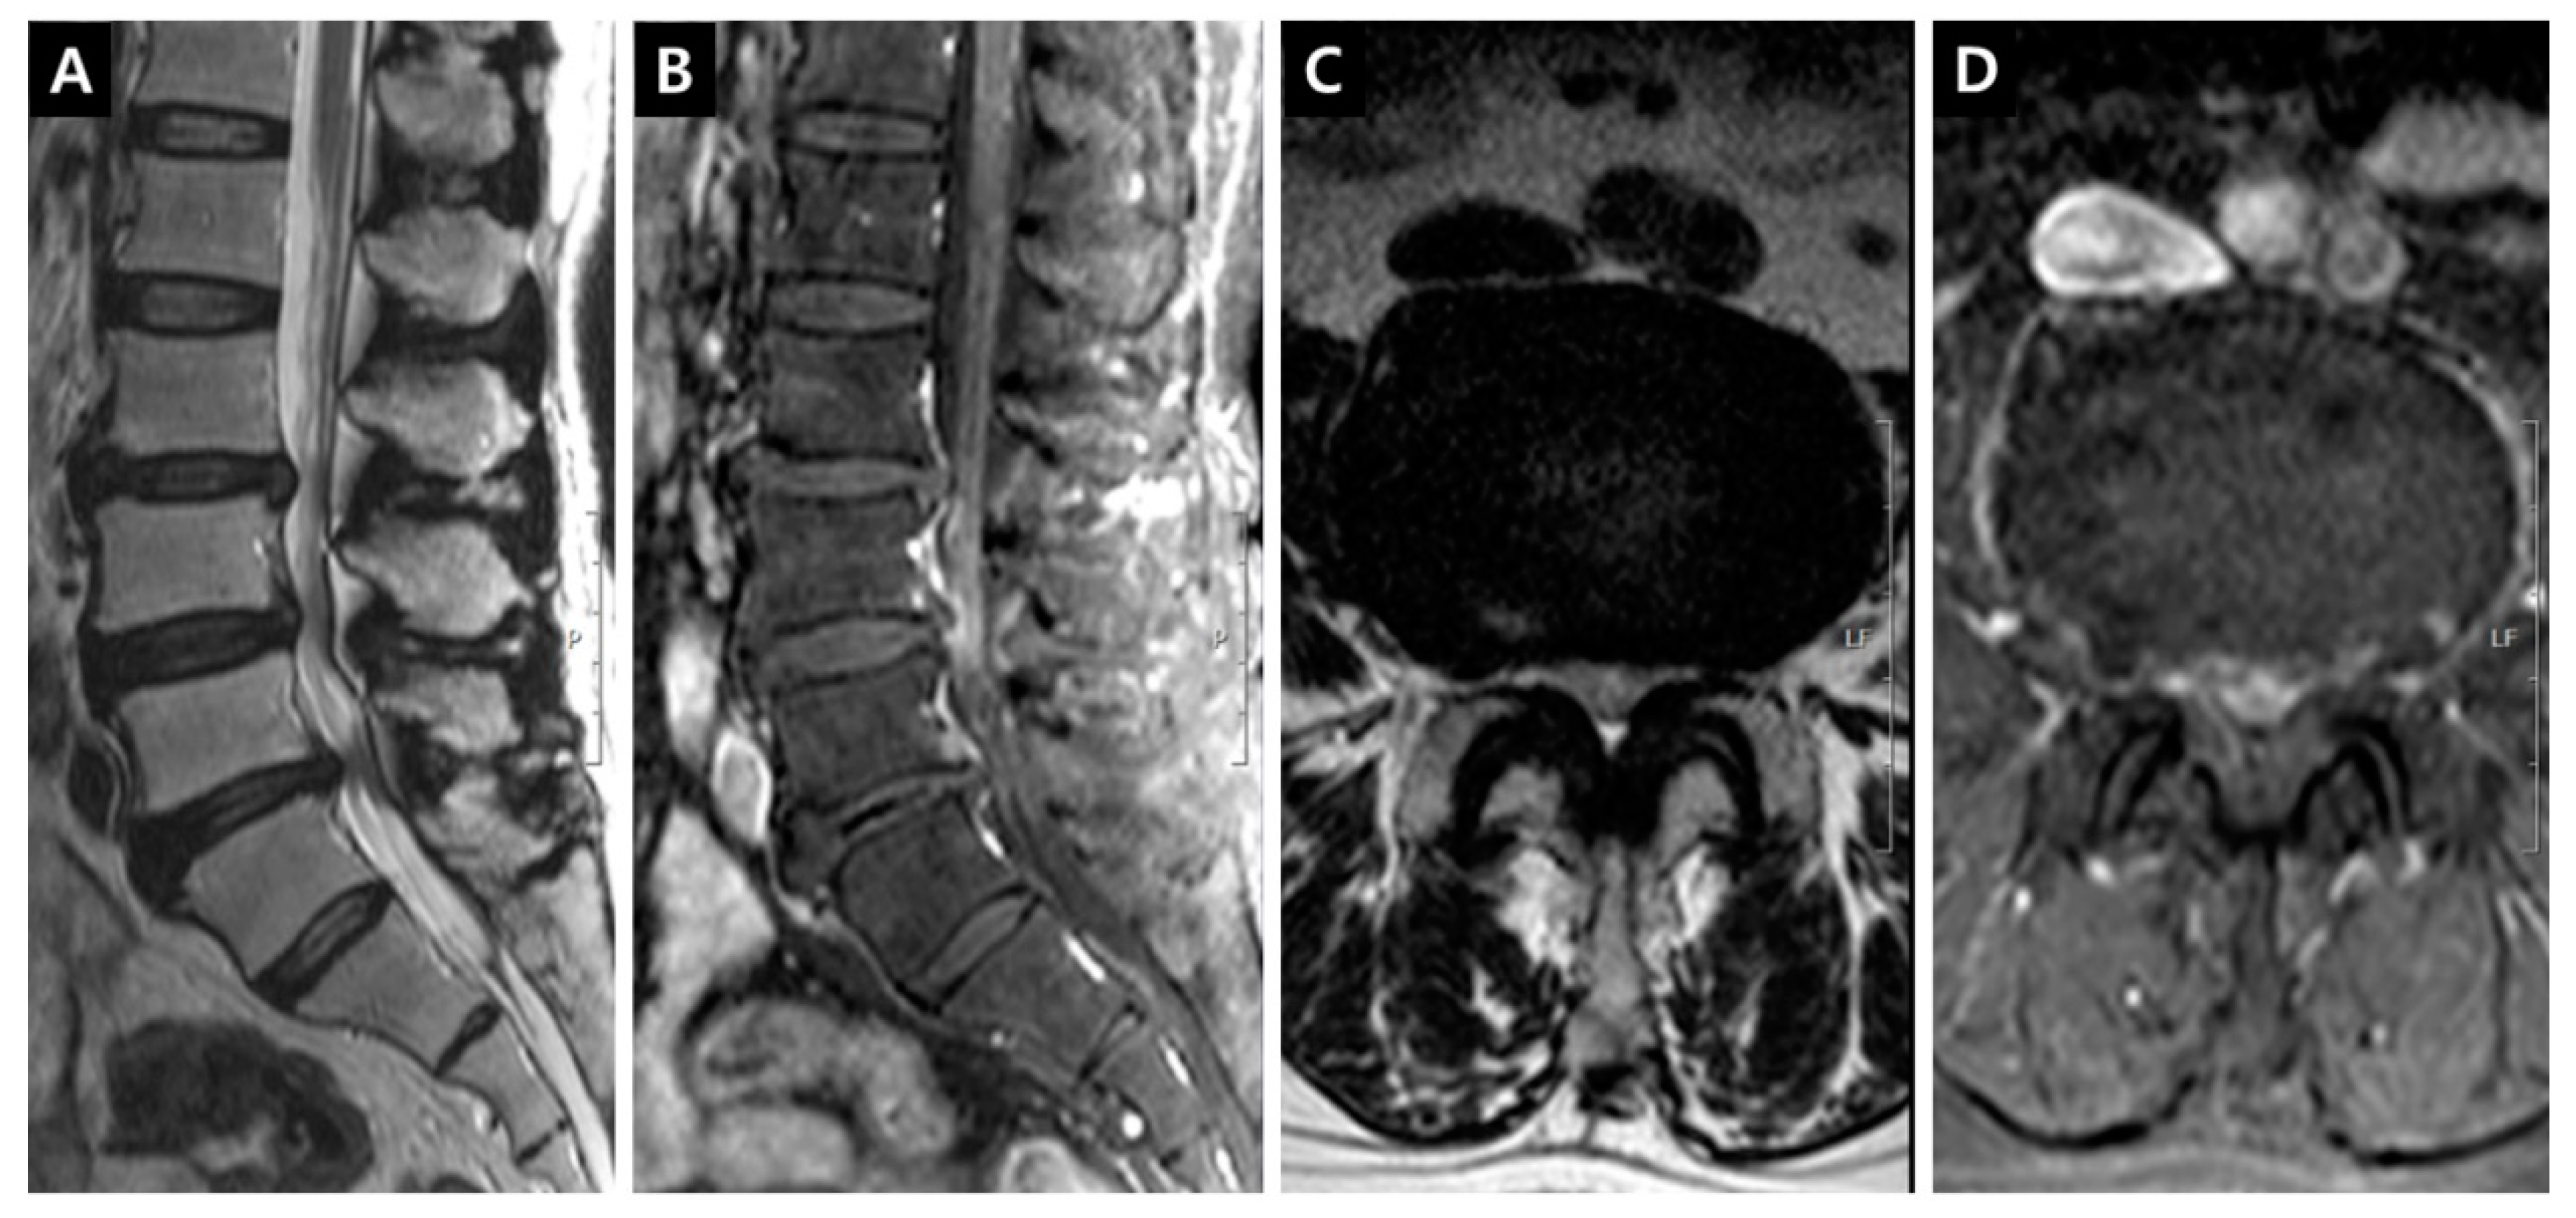

Figure 2. Enhancement patterns: periradicular vein (PVCE). (A) T2-weighted right parasagittal image showing the origin of right L5 traversing root; (B) Fat-suppressed enhanced T1-weighted right parasagittal image indicating the periannular enhancement on the right subarticular L4-5 annulus; (C) T2-weighted axial image on the L5 upper endplate level; (D) Fat-suppressed enhanced T1-weighted axial image on the L5 upper endplate level, the definite periradicular enhancement around the right L5 traversing root can be seen in the lateral recess.

DCSAs were measured on the T2-weighted axial plane at the most stenotic level in all stenosis groups and at the L3–4 and L4–5 levels in the control group. The presence of enhancement patterns such as PVCE, DVCE, and IRCE was assessed qualitatively at the level of stenosis. PVCE indicated the enhancement of the periradicular vein and was regarded as a part of the longitudinal vein in anterior IVVP or PEVC (Figure 2). DVCE designated the enhancement of the dorsal epidural venous plexus in the posterior IVVP (Figure 3). IRCE indicated the enhancement of the intraradicular vein within intrathecal rootlets (Figure 4). The author assumed that these enhancement patterns (PVCE, DVCE, IRCE) developed according to the degree of venous congestion and reflux.